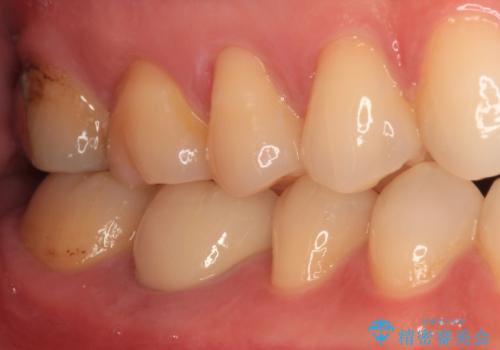

腫れていた歯茎は根管治療後に解消され、適合の良いセラミッククラウンを装着することができました。